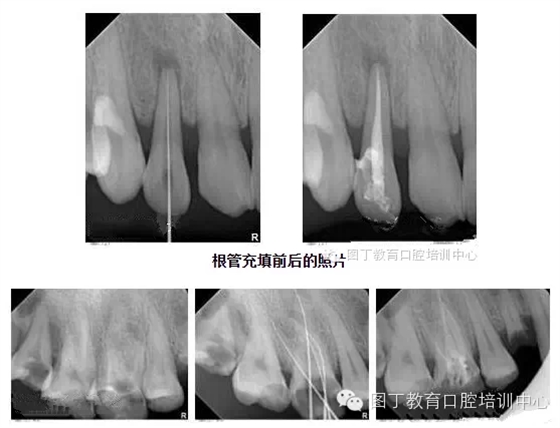

4、關(guān)于根管充填

總結(jié)幾個(gè)要點(diǎn):

1,根管充填到位的前提是根管要預(yù)備好;

2,把握好充填長(zhǎng)度;

3,選擇合適的主膠尖意義很大——合適的主尖其尖端恰好封閉根尖孔;

4,糊劑適量即可,因?yàn)槌涮畹闹黧w是牙膠。

5,側(cè)方加壓后的垂直加壓不可忽視,因?yàn)橥ㄟ^(guò)垂直加壓后的充填體更嚴(yán)實(shí)。